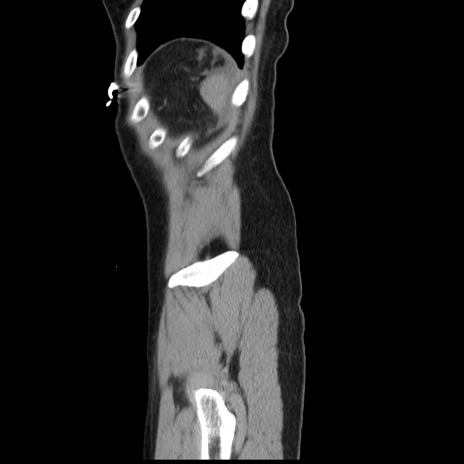

横断像